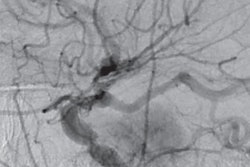

ASL-MRI maps show regions of the brain in which cerebral blood flow was greater in patients with chronic kidney disease than normal subjects. The areas (red, yellow, and orange) are associated with cognitive function. Image courtesy of Radiology and RSNA.In addition, there were no brain regions in which the control subjects showed significantly higher cerebral blood flow than the patients with chronic kidney disease.